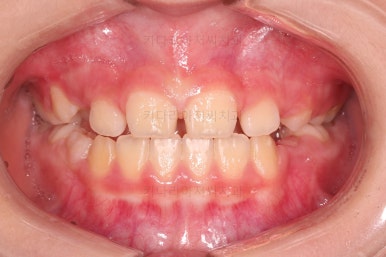

치료 22개월 째 종료시점의 사진입니다.

전후 비교해 볼게요.

교합도 좋아졌고 앞니 관계(반대교합, 개방교합)도 개선이 잘 되었어요.

얼굴모습도 특유의 아래턱 부위가 길어보이고 나와보이던 느낌이 완벽히 개선되었네요.

웃는 모습도 참 예뻐졌고, 이제는 약간의 주걱턱 느낌도 전혀 보이지 않습니다.